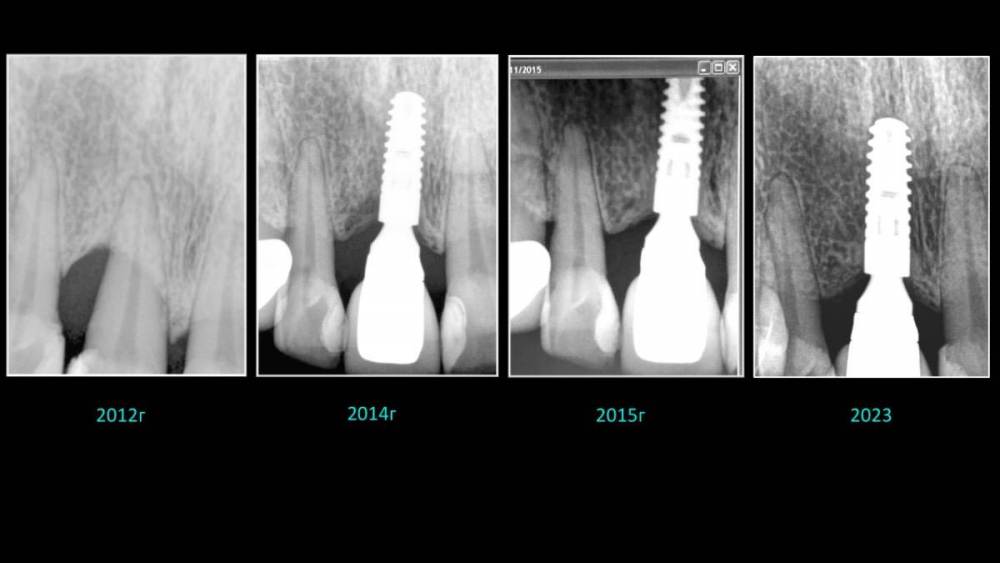

Владмир Опубликовано 20 марта, 2023 Автор Поделиться Опубликовано 20 марта, 2023 Здравствуйте коллеги. Работе 10 лет. Фото начальных этапов добавил 7 1 2 Ссылка на комментарий